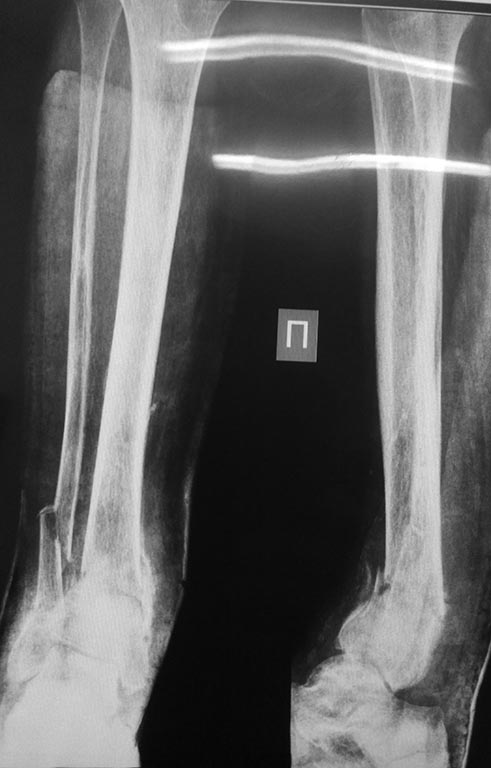

Перелом костей голени в нижней трети

Добрый день!Обратилась женщина 1958 г.р.Травма 08.09.16. Почувствовала боль в правой голени во время сна.

Лечилась амбулаторно с Ds: закрытый перелом костей правой голени в нижней трети без смещения. Повторную травму исключает. На контрольных Rg выявлено смещение отломков, признаки консолидации.

в анамнезе сахарный диабет I типа в течении 29 лет. лабильное течение. Диабетическая нефропатия. ХБП V ст. ХПН терминальная стадия. Хронический програмный гемодиализ. Ренальная остеодистрофия. Принимает лантус 6 Ед *1 раз в сутки. уровень сахара крови 12-15 ммоль\литр. Креатинин 543 мкмоль\литр, ЩФ 1270 Е\л.

А Вы то какой диагноз ставите? От чего сломалось? Ренальная остеодистрофия на фоне ХПН с гемодиализом? Диабетическая остеоартропатия? Пишете, что повторную травму исключает. Но и первичной не было. Последняя рентгенограмма (где перелом без смещения) когда была сделана? Сразу после обнаружения перелома? Там уже есть признаки консолидации. Есть ли признаки периферической нейропатии? Если не вдаваться в подробности, то можно думать об остеосинтезе двойного перелома наружной лодыжки (вероятно, уже срослась). И интрамедуллярном остеосинтезе большеберцовой кости.